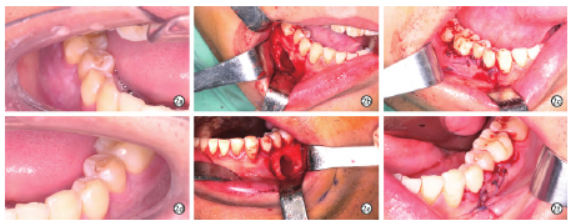

完善术前检查,排除手术绝对禁忌症后,术前与患者沟通治疗方案,患者要求先行囊肿刮除手术,择期完成45根管治疗。在全麻下行“双侧下颌骨囊性病变刮治术”(图2)。术后病检为:左下颌骨符合牙源性发育性囊肿伴感染;右下颌骨纤维性囊壁内见大量炎症细胞及泡沫细胞浸润,未见上皮衬里,免疫组化结果显示:TLE1(-)(图3)。

图2 双侧下颌骨囊肿刮治术中照片。2a~2c:右侧下颌骨囊肿翻瓣前、囊肿刮除后、缝合术区;2d~2f:左侧下颌骨囊肿翻瓣前、囊肿刮除后、缝合术区